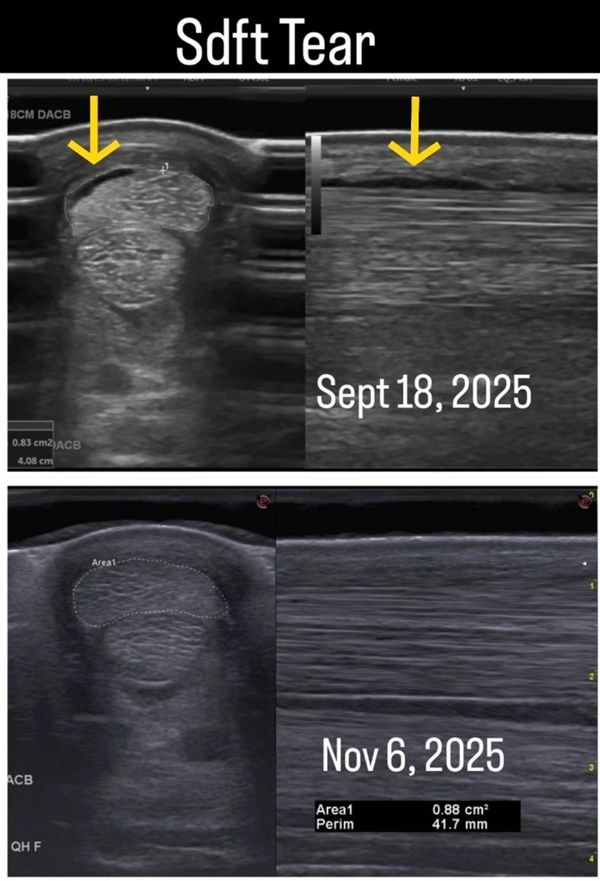

Horse was diagnosed with SDFT injury September 18, 2025, Acuscope/myopulse treatment started September 23, 2025, recheck ultrasound performed November 6, 2025.

This horse was diagnosed via ultrasound on September 18, 2025 as having 𝐭𝐰𝐨 𝐥𝐞𝐬𝐢𝐨𝐧𝐬 along the SDFT on the RF, one lesion at the musculocutaneous junction in the carpal canal and one peripheral irregularity in the fibers at level of the proximal metacarpus. The horse has been on stall rest, began treatment with me on September 23, 2025, with a hand walking regimen. The owner was in full compliance with the veterinary and my protocol of a moderate to aggressive rehabilitation program and kept the horse controlled to ensure she did not reinjure or disturb the fibers further. She also provided quality forage based, balanced diet (VERY important), along with omegas and vitamin e. In this case the owner works in vet med, but is also a farrier. The owner provided diligent hoof care to ensure the horse’s angles were correct as to not put any more strain on the tendon.

During the FIRST recheck on November 6, 2025 in summary, the veterinary noted that now there is no significant injury within the carpal canal, except for some thickening of the flexor retinaculum. The SDFT is normal size along its length. There is only a thin hypoechoic area along the palmar margin of the SDFT in the proximal metacarpal region with minimal irregular fibers, with the remainder of the SDFT being “unremarkable” (aka nothing wrong). Evidence of 𝒆𝒂𝒓𝒍𝒚 𝒉𝒆𝒂𝒍𝒊𝒏𝒈 was noted of the SDFT with some remaining inflammation that needs to dissipate.

This is visually seen within the ultrasound depicted. The arrows are signifying where the initial lesions/tears were on Sept. 18th and below is the new ultrasound of the same area from Nov. 6th where you can see 𝐧𝐨 𝐞𝐯𝐢𝐝𝐞𝐧𝐜𝐞 𝐨𝐟 𝐭𝐡𝐞 𝐥𝐞𝐬𝐢𝐨𝐧𝐬 (except for possibly a very tiny area if we are being picky). These ultrasounds are from the proximal aspect of the SDFT, there was nothing left to compare images of the lesion within the carpal canal.

𝐓𝐡𝐢𝐬 𝐰𝐚𝐬 𝐝𝐨𝐧𝐞 𝐰𝐢𝐭𝐡𝐢𝐧 𝟔 𝐰𝐞𝐞𝐤𝐬. For reference, for a SDFT tear (keep in mind this case being 2 lesions) normally the rehabilitation time generally falls somewhere between 6-12 months depending on the severity of the injury and remodeling (final phase of healing) of the SDFT generally doesn’t take place until at least 4 months if not more. Horses are generally not allowed ridden work until around the 4 month time frame due to this fact, pending the healing is improving. Whereas in this case my client is starting to gradually return her horse to load bearing (ridden) exercise after the 1st recheck at only 6 weeks of rehabilitation.